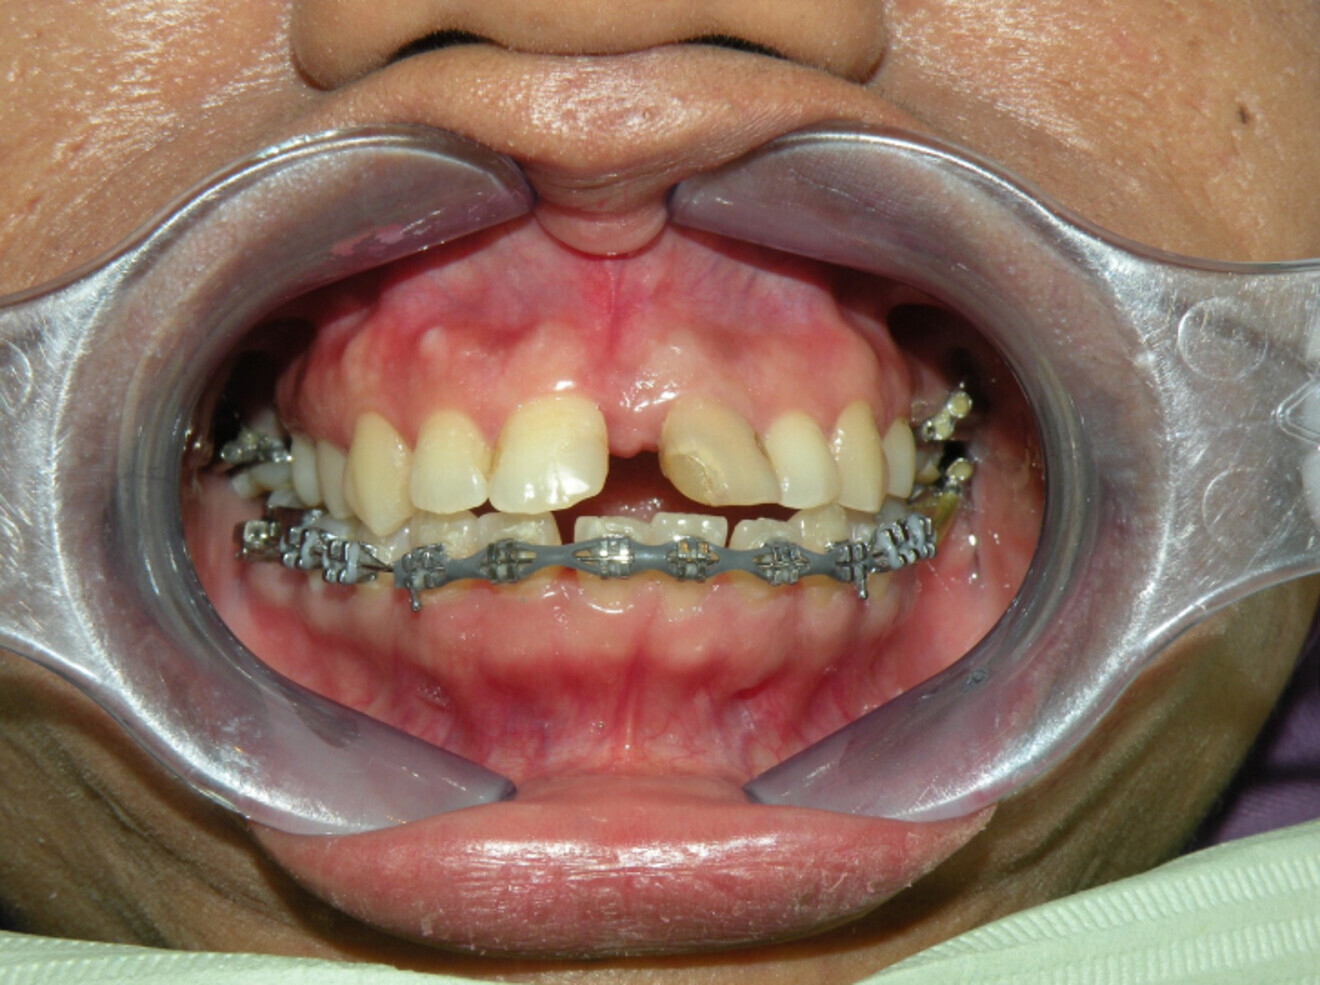

Treatment Plan:

– Upper lower conventional metal MBT brackets.

– Posterior spaces to be maintained for future implants.

– 2-unit bridge before debonding.

– Essix retainer upper lower for retention.

Fig. 12a: Lower arch bonded first to collapse in pursue of overjet and overbite.

Fig 12b:  Upper arch bonded once spaces in lower arch managed.